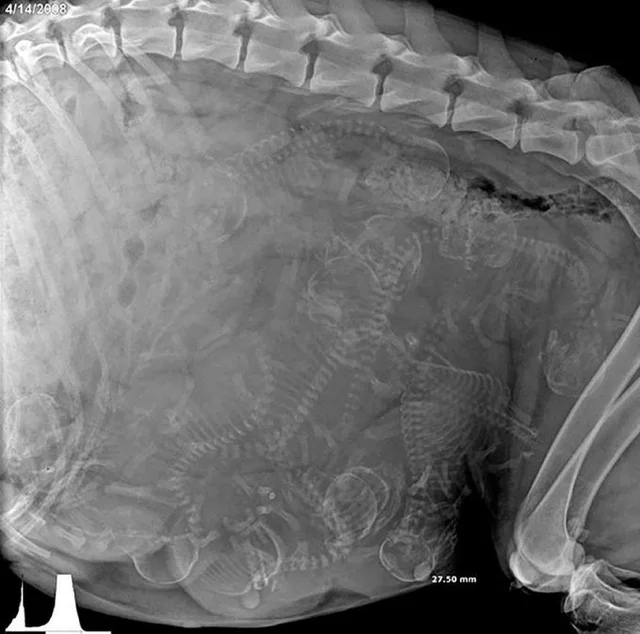

9. Рентгеновский снимок беременной собаки